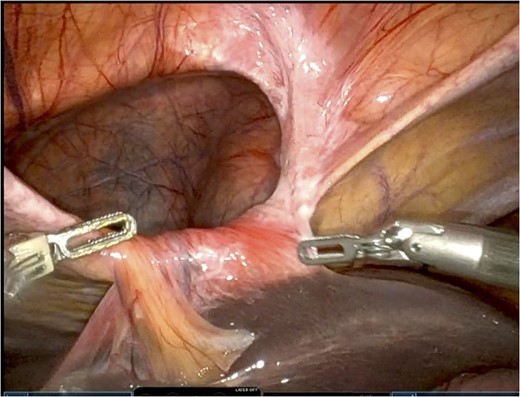

The falciform ligament was taken down with bipolar cautery. A peritoneal flap was created commencing about 4 cm inferior to the defect. A preperitoneal dissection was then performed to create the flap and to reduce the sac out of the mediastinum (Fig. 4).

Care was taken to avoid injury to the pleura and the pericardium. Once the sac was reduced, the defect’s size was measured as 9 cm in horizontal length by 4 cm in vertical dimension. Primary closure of the defect was performed with a running 0 V-loc absorbable 180 suture.